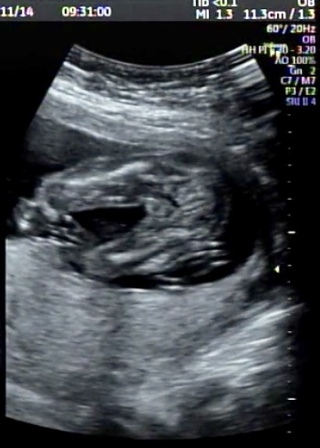

妊娠18週6日 18w6d の超音波 エコー 写真

妊娠18週1日 18w1d の超音波 エコー 写真

医師監修 妊娠18週のエコー写真を多数掲載 みんなのエピソードつき マイナビウーマン子育て